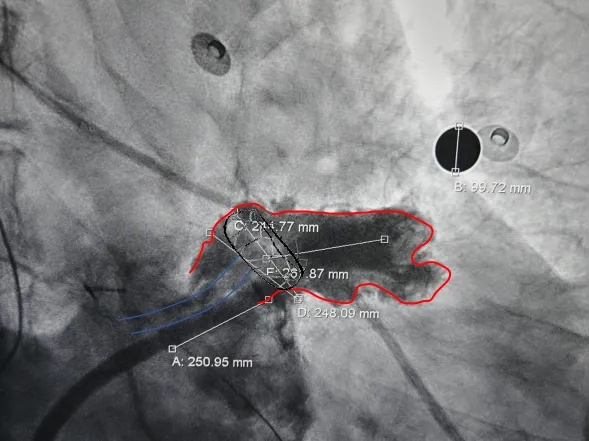

牵拉稳定,且造影无残余分流。

造影后无残余分流

多角度观察心包积液情况,无新增心包积液,同时封堵器稳定封堵心耳口部。

术前结合CT以及术中造影评估左心耳开口24.9mm,深度26.9mm,心耳内部空间合适,且患者全身情况良好,可较配合局部麻醉手术,采用极简式封堵术安全可行。术中考虑心耳开口和深度充足,可利用心耳空间进行退鞘释放封堵器,使封堵器完全封堵左心耳。术中LAFDQ-26封堵器释放时上缘未挂住梳状肌,下缘露肩,导致牵拉不稳定,选择LAFDQ-29封堵器再次尝试,封堵器展开后放置位置合适,且牵拉稳固,术后封堵器形态完整,即刻造影,未见残余漏。封堵器压缩比为10.7%,压缩合适,术中符合PASS原则,释放封堵器,术后封堵器稳固锚定在心耳壁,封堵器与心耳紧密贴合,无过度扩张风险,显著提升封堵完整性。